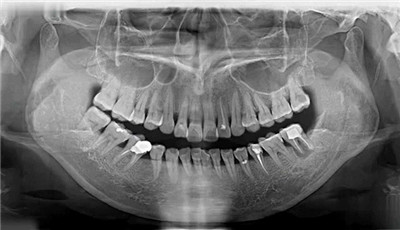

是修复牙齿缺失的首选方式

种植牙的突显优势

1、作用强:能非常好地修复牙齿咀嚼功能,吞咽作用大大的好于传统活动假牙。

2、不磨牙:无需磨周围的身心健康牙齿,独立存在于牙龈。

3、固位好:种植体与牙龈牙槽紧密联系,像原生牙一样作用于口腔,具备较强的固位力与可靠性。

4、美观大方:能够依据就诊者的脸型、牙齿形态与色调订制牙冠,实际效果非常融洽。

5、舒服便捷:无基托卡环,无异物不适感,十分舒服、便捷,且有益于维持口腔的日常保洁。

6、手术痛苦小:种植牙手术是一项微创外科手术,相近拔牙但是比拔牙的痛感还低,外伤小,出血少,无需住院,手术后就可以进餐,麻药过了有些微胀痛感,在可承受范围内,基本可以说没有什么痛苦!